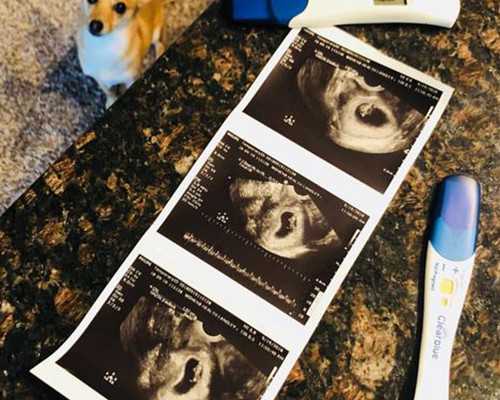

- 驗(yàn)孕試紙什么時(shí)候能測(cè)出懷孕?

- 驗(yàn)孕棒和抽血,哪個(gè)結(jié)果更準(zhǔn)?

- 驗(yàn)孕試紙準(zhǔn)不準(zhǔn)?什么時(shí)候用最合適

- 驗(yàn)孕試紙一個(gè)月后測(cè)準(zhǔn)不準(zhǔn)

- 驗(yàn)孕棒怎么用才準(zhǔn)?手把手教你正確操作

- 早早孕試紙?jiān)趺从茫窟@些細(xì)節(jié)你得知道

- 早孕試紙?jiān)趺从煤涂唇Y(jié)果?簡(jiǎn)單幾步教會(huì)你

- 早孕試紙去哪買更放心?

- 早孕試紙的正確用法,這些細(xì)節(jié)你可能不知道